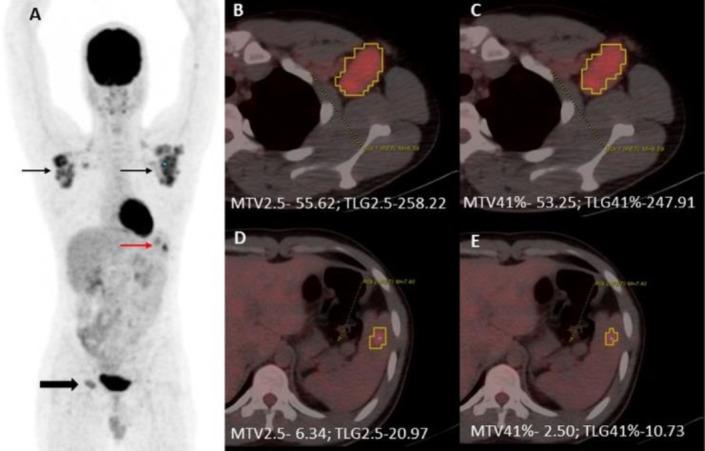

At a median follow-up of 48.83 months (IQR:33.31-63.05 months), the five-year-EFS was 81%. Of the 100 patients, 16 had relapsed (16%) and none died at the last follow-up. On Univariate analysis, among non-PET parameters bulky disease (P=0.03) and B-symptoms (P=0.04) were significant while among PET/CT parameters SUV (p=0.001), SUV (P=0.002), WBMTV2.5 (P<0.001), WBMTV41% (P<0.001), WBTLG2.5 (P<0.001) and WBTLG41% (P <0.001) predicted poorer EFS. 5-year EFS for patients with low WBMTV2.5 [<1038.3 cm3] was 89% and 35% for patients with high WBMTV2.5 [≥1038.3 cm3] (p <0.001). In a multivariate model, only WBMTV2.5 (P=0.03) independently predicted poorer EFS.

中位随访时间为48.83个月(四分位间距:33.31 - 63.05个月),五年EFS为81%。100例患者中,16例复发(16%),末次随访时无死亡病例。单因素分析显示,在非PET参数中,大包块病(P = 0.03)和B症状(P = 0.04)具有统计学意义,而在PET/CT参数中,标准化摄取值(SUV)(p = 0.001)、SUV(P = 0.002)、全身代谢肿瘤体积2.5(WBMTV2.5)(P < 0.001)、WBMTV41%(P < 0.001)、全身总病变糖酵解2.5(WBTLG2.5)(P < 0.001)和WBTLG41%(P < 0.001)提示EFS较差。WBMTV2.5低[<1038.3 cm³]的患者5年EFS为89%,WBMTV2.5高[≥1038.3 cm³]的患者为35%(p < 0.001)。在多变量模型中,只有WBMTV2.5(P = 0.03)独立预测EFS较差。